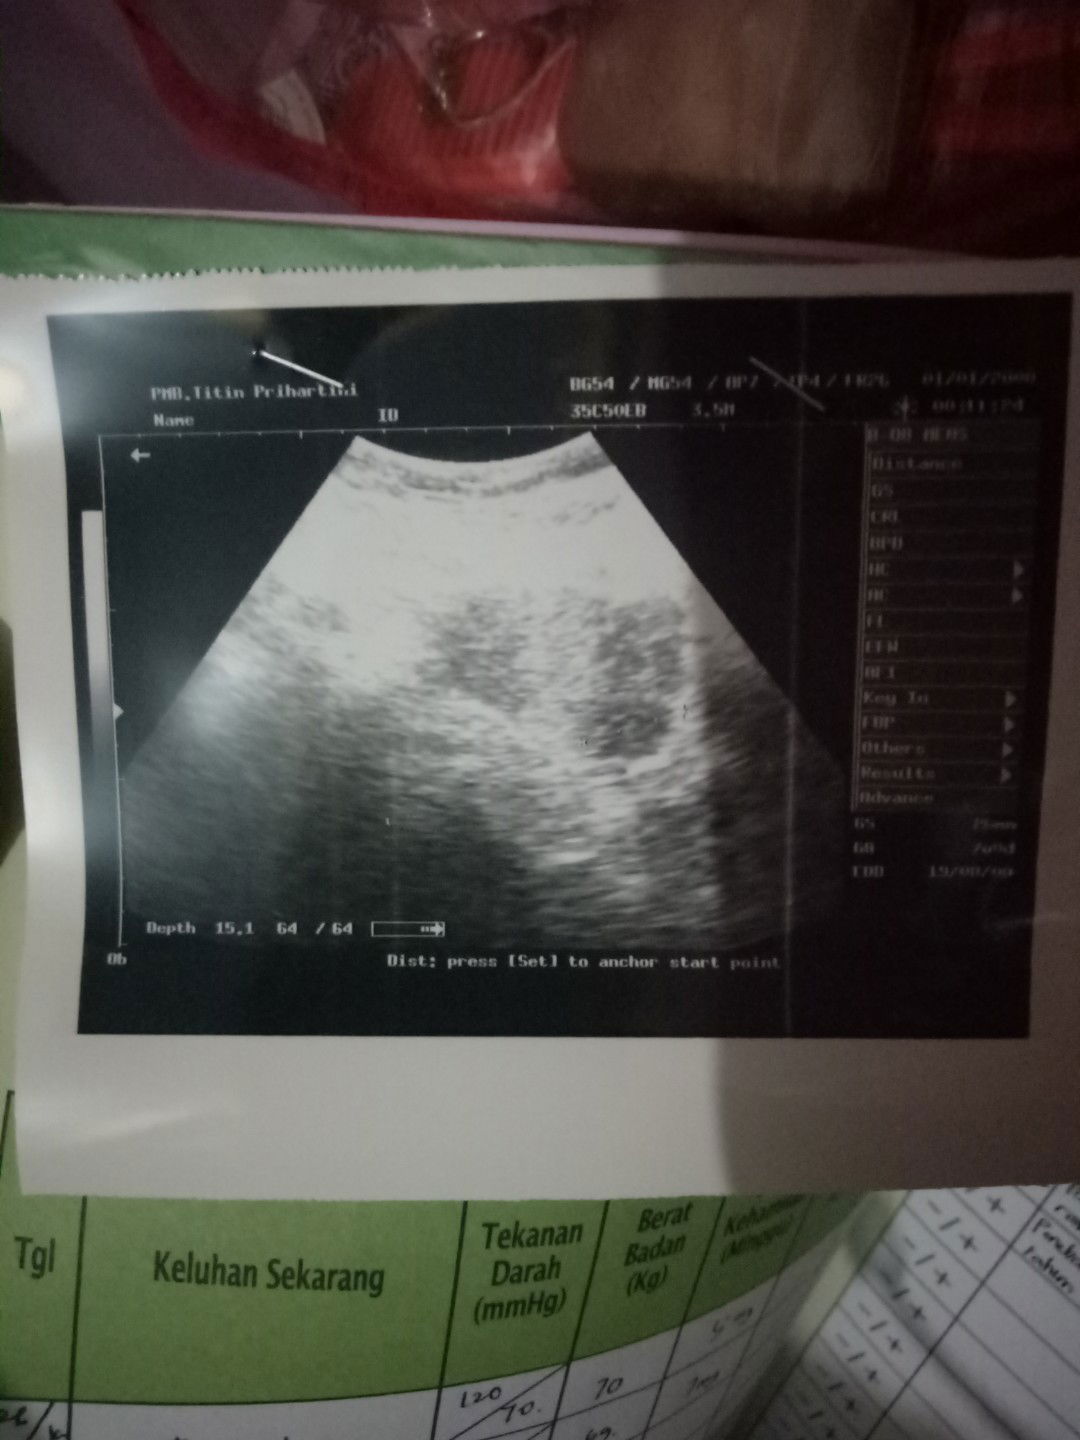

penebalam rahim

Wajar engga ya 7week masih penebalan rahim belum terlihat kantong rahim nya